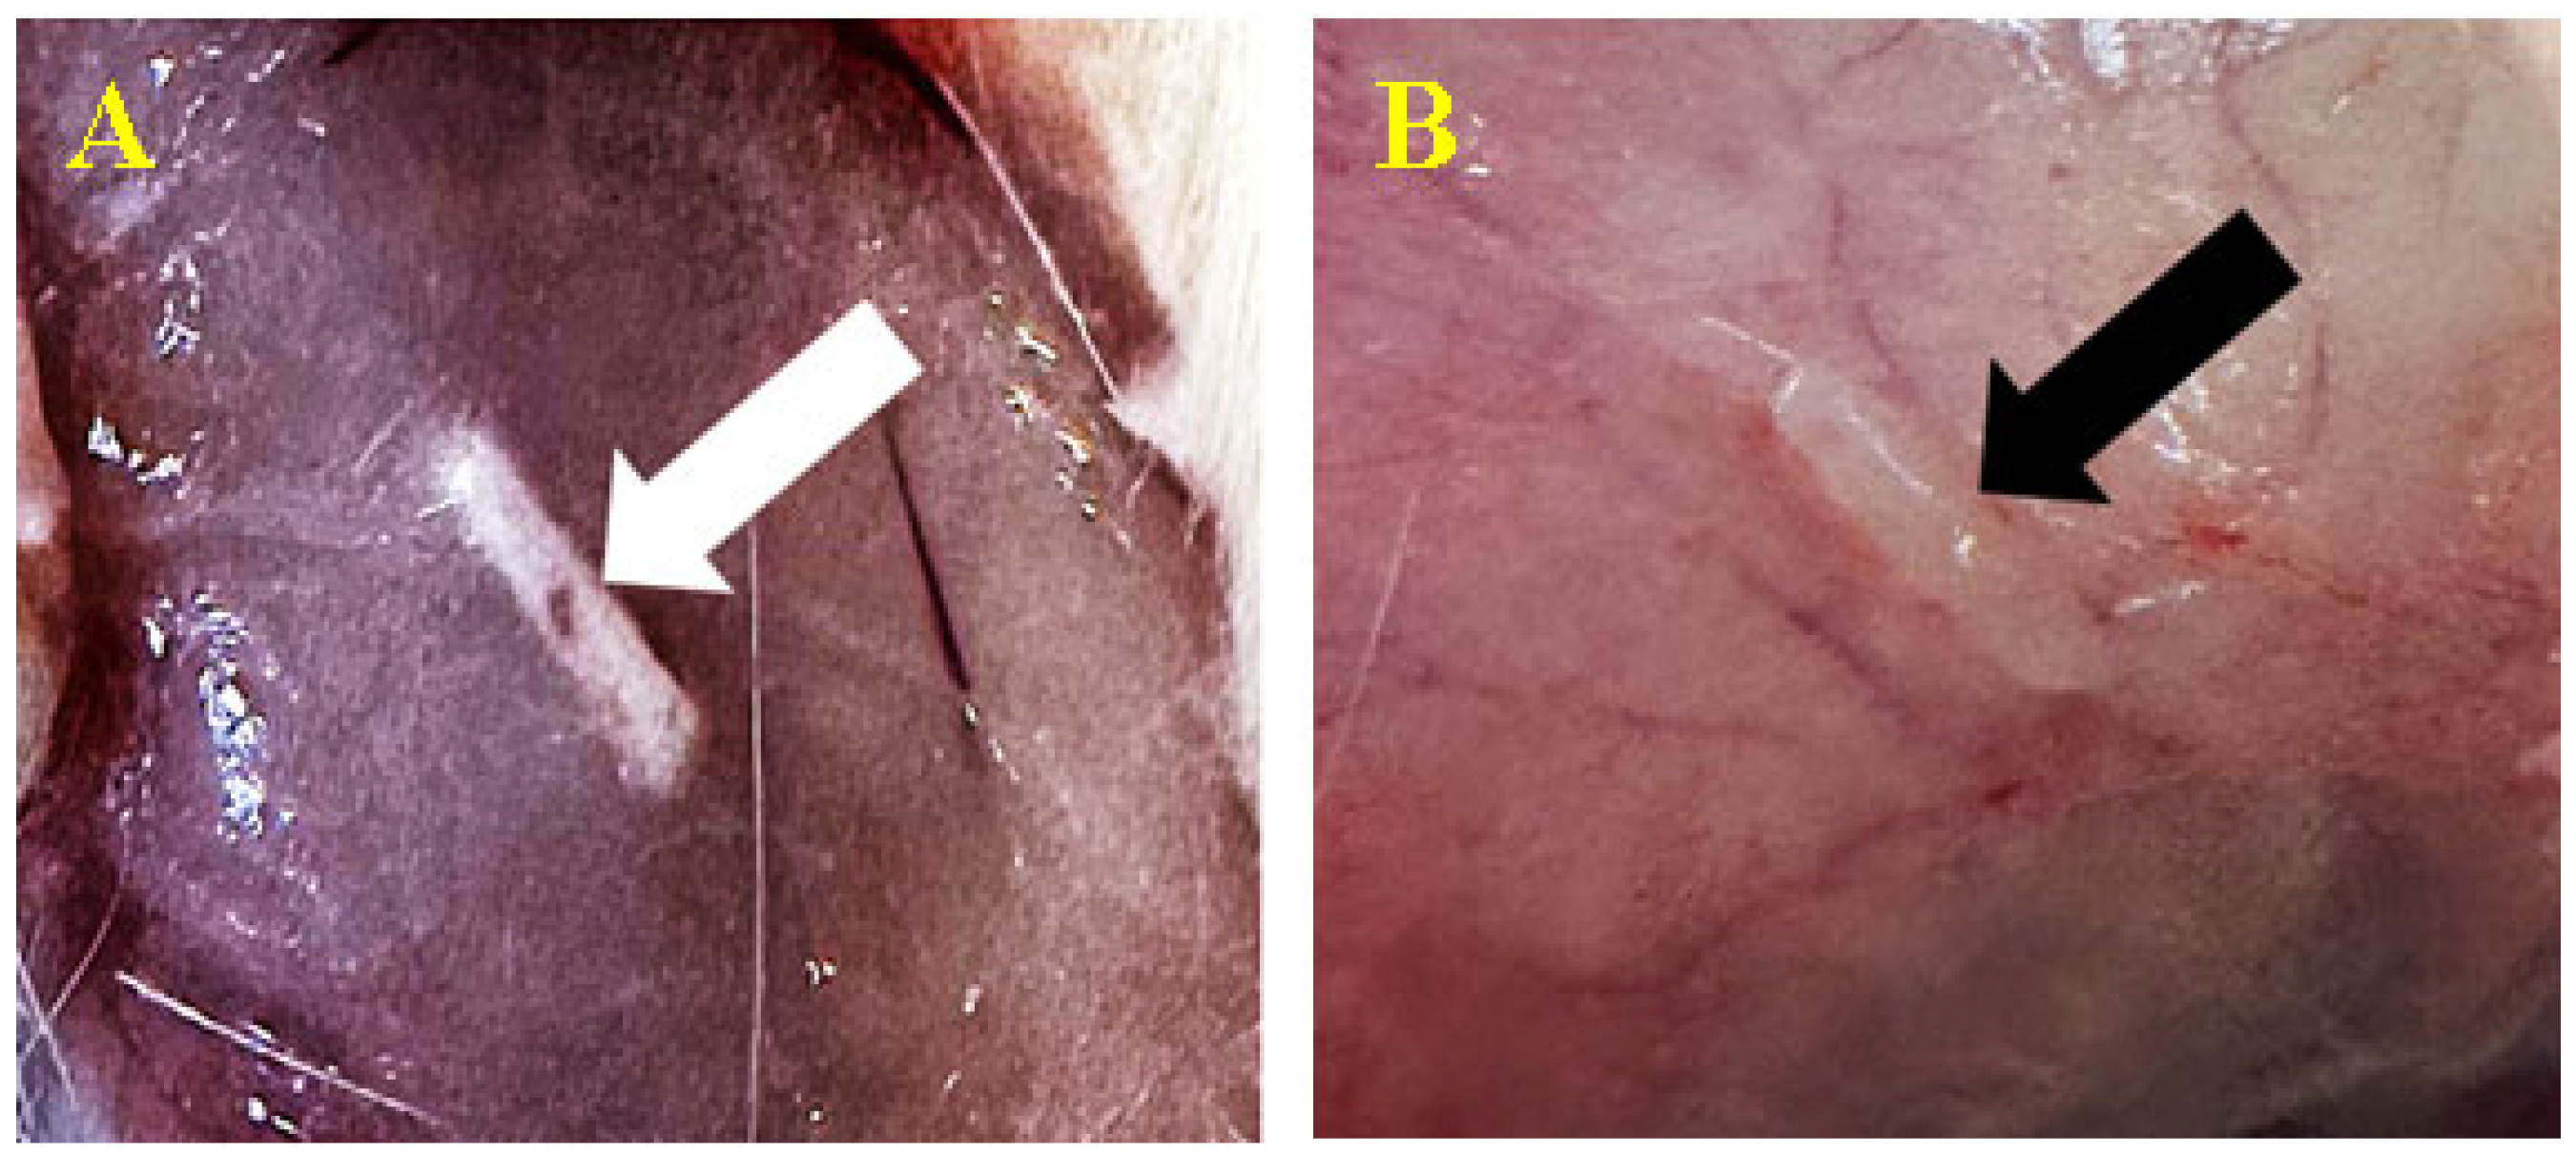

3.3.1. Subcutaneous

3.3.2. Peri/Intramuscular